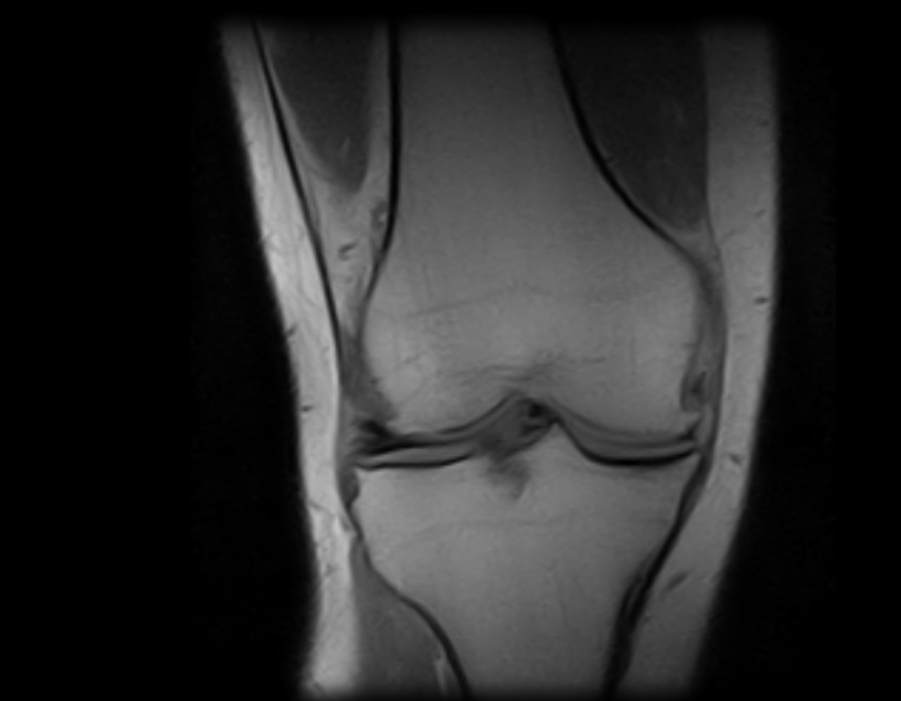

Imágenes Clínicas

El S-scan permite resonancias magnéticas cerebrales gracias a su amplia gama de aplicaciones a través de bobinas dedicadas.